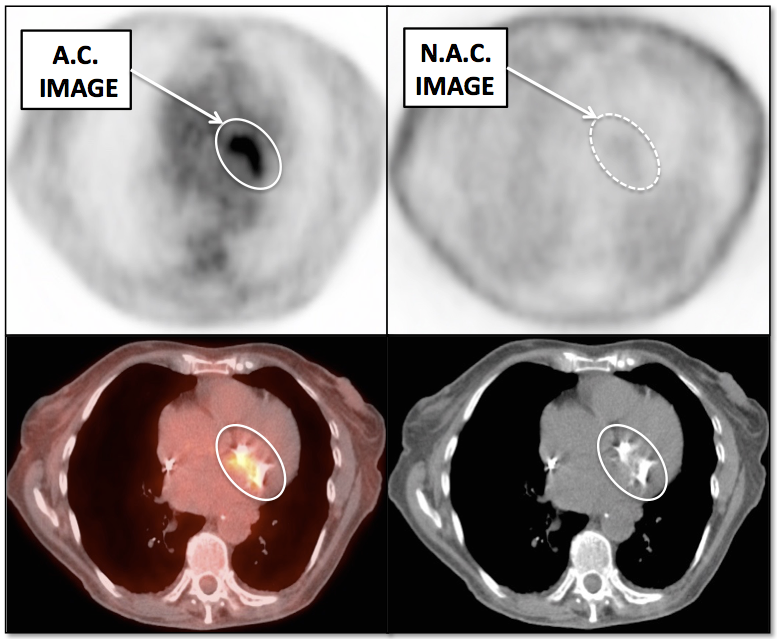

Value of Non-Attenuation Corrected (NAC) Images

Resolving Attenuation Correction Artifacts:

The CT images obtained during an exam are not only used for “anatomic” interpretation. They are also used for “attenuation correction” (AC) of the PET images, generating the much more useful AC PET images used for interpretation.

Unfortunately, attenuation correction of PET images can result in falsely elevated metabolic activity in regions of high CT density (e.g. metallic devices, oral contrast, calcification).

In such cases, these areas must be reviewed on the NAC (non-attenuation correction) images. If these regions are not also hypermetabolic on the NAC images, then their apparent increased FDG-uptake on the AC images is artefactual.

Lung Nodule Identification:

NAC images can occasionally be useful in identifying mild to moderately FDG-avid lung nodules, especially those located in the lung periphery or lung bases.